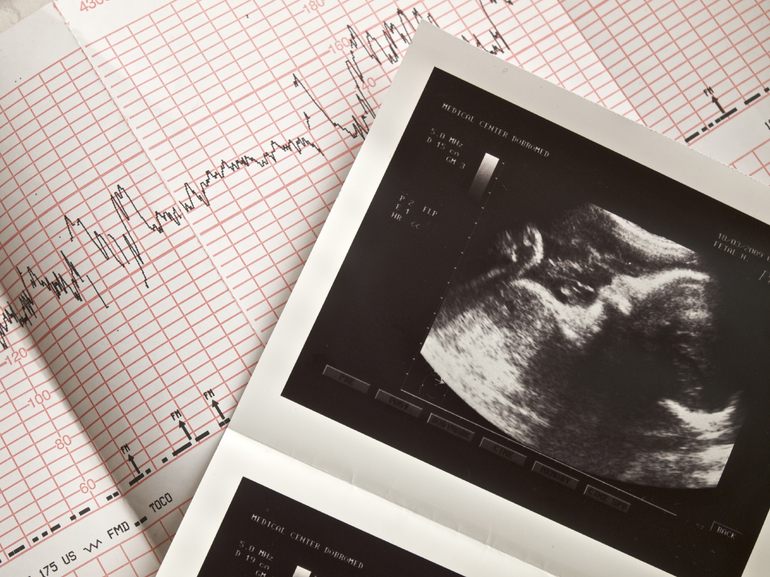

- С помощью УЗИ прослушивается стук сердца эмбриона на 4−5 неделе. Если на этом сроке доктор ничего не услышал, возможно, биение появится немного позже. При повторном обследовании отсутствие сердцебиения может говорить о замершей беременности, которая должна прерываться медикаментозно. Заводить ребёнка повторно рекомендуется только через полгода.

- Проведением кардиографии (КТГ). Этот метод позволит узнать не только частоту сердцебиения, но и определить кислородное голодание плода. А в случае обнаружения патологий оказать своевременную помощь. Аппарат оснащён датчиками сокращения матки, движений плода, а также основными датчиками, отражающими сигналы от сердца, которые записываются на плёнку. Весь процесс занимает приблизительно 60 минут. КТГ проводят на 32-й неделе и перед родами. В течение всей беременности делают только по показаниям. Этот метод не вреден ни матери, ни ребёнку, поэтому его можно проводить необходимое количество раз. Если пульс плода в утробе матери 120−160, а при шевелении увеличивается, значит всё в порядке. Но на КТГ могут возникать и изменения вследствие гипоксии плода. ЧСС увеличивается, когда не хватает кислорода, либо уменьшается, если происходит схватка или шевеление. Это ненормально и требует консультации опытного доктора. А также может происходить прижимание пуповины к головке малыша. Тогда результаты будут такими же, как и при гипоксии, но плод чувствует себя при этом хорошо. Ещё изменения в КТГ могут быть вызваны неправильным прикреплением датчиков или их поломкой. Если гипоксия выявлена и при повторном проведении, то врач решает, как проводить лечение.